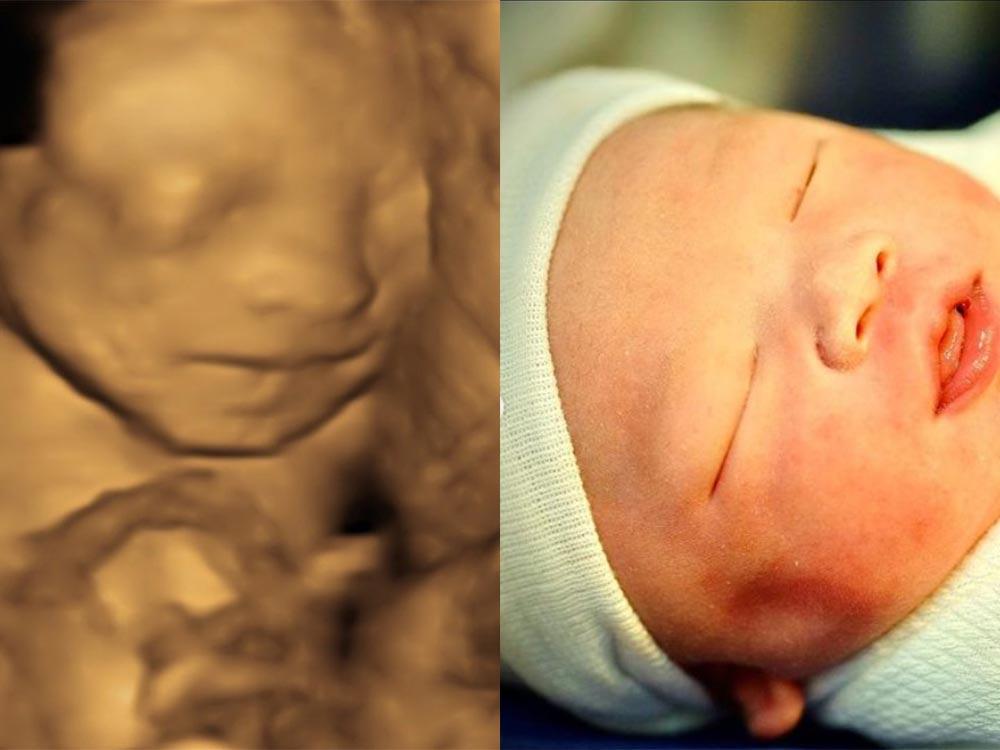

Celebrity babies: Sonogram vs. actual photos

Fortunately, some of these celebrities constantly update their followers about their pregnancy journey, which include showing in public the sonogram, which is an ultrasound picture, of their child.

Check out the sonogram of these celebrity babies and how they look like upon giving birth in this gallery.